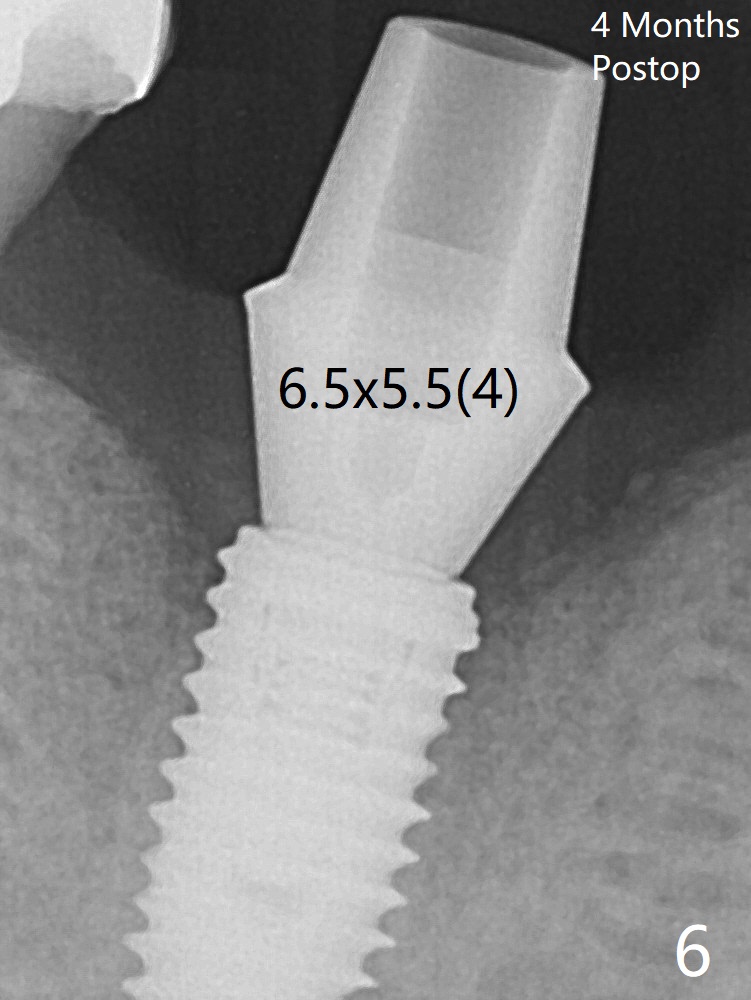

A 6.5x5.5(4) mm cemented abutment is seated and torqued at 30 Ncm before impression (Fig.6).